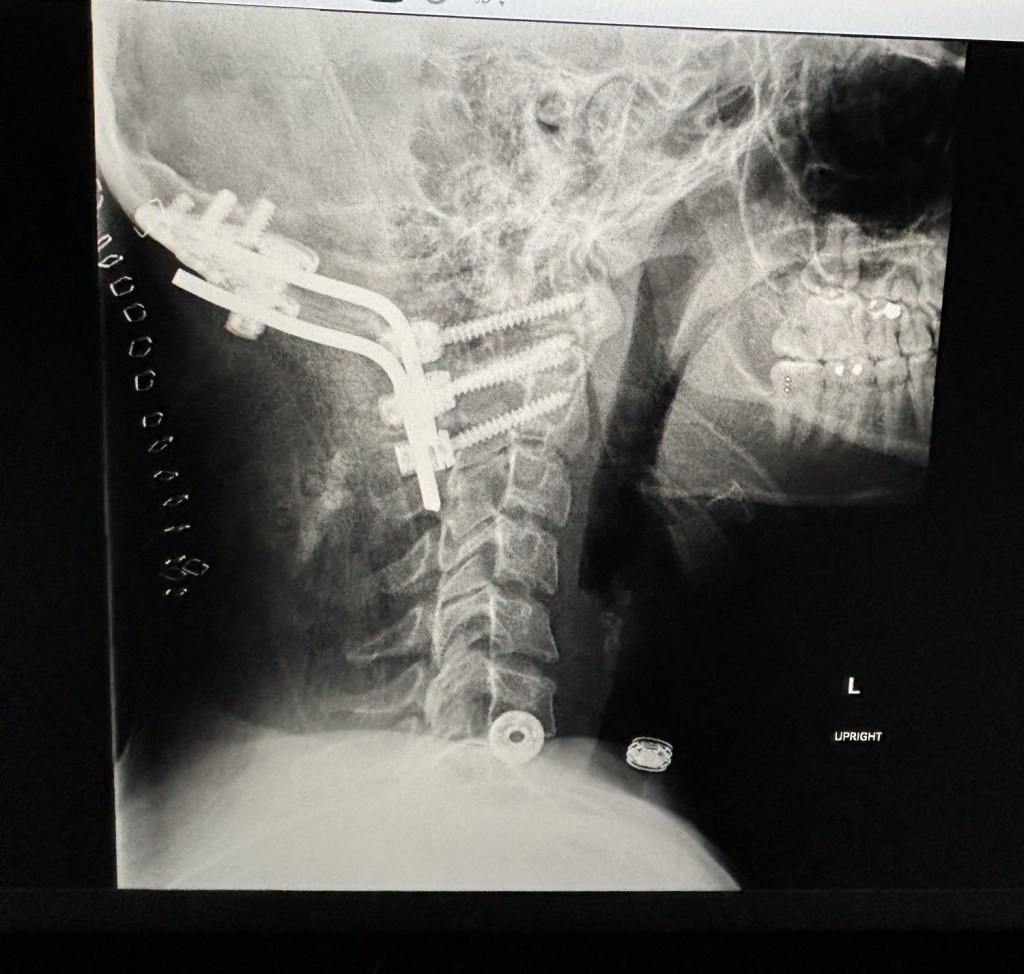

Finally, the time came to meet with the neurosurgeon. He is pleased with my progress. My scar is healing very well. The x-rays show that all the screws are in place and exactly where they need to be. We talked through my symptoms and how to treat or monitor them. We talked through the scary symptoms that sent me to the ER at OHSU. He had a fresh take and thinks they are related to post-surgical complications, not nerve damage. Most of the symptoms, he thinks, can be managed by medication and physical therapy. It was really good news and an answer to my prayer. Thank you everyone for praying with me for healing and through this very stressful time.

I’m now able to lift 10 pounds and can start weaning off the neck brace. My neck muscles are very weak, so it’s going to be a slow process. The brace has a knob in the front that you can pull up and twist to adjust it up or down. Right now, the brace is supporting my head. During the day, I’m going to start turning the knob to make it loose, and then when my neck gets fatigued, adjust it back up (beginning with 2–5 minutes).

At 12 weeks, in December, I’m going to have a CT to check the bone graft and make sure it is still in place. That will also be when I have another check-in with the surgeon virtually.